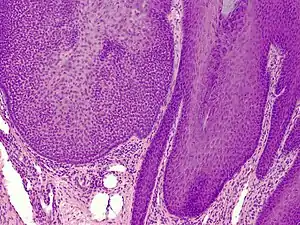

Trichilemmoma

Trichilemmoma (also known as "tricholemmoma"[1]) is a benign cutaneous neoplasm that shows differentiation toward cells of the outer root sheath.[2]: 673 [3] The lesion is often seen in the face and neck region. Multifocal occurrence is associated with Cowden syndrome, in which hamartomatous intestinal polyposis is seen in conjunction with multiple tricholemmoma lesions.

A trichilemmoma on a forehead